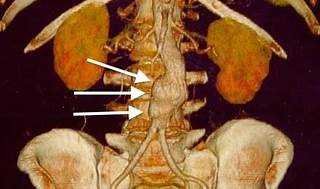

Acute renal failure is one of the possible complications of abdominal aortic aneurysm (AAA) repair, especially after open surgery. Acute renal failure is a sudden loss of kidney function that can cause fluid and electrolyte imbalance, acid-base disturbance, and uremic syndrome. Acute renal failure can occur due to several factors, such as hypoperfusion of the kidneys, atheroembolism, contrast- induced nephropathy, or ischemia-reperfusion injury.

The incidence of acute renal failure after AAA repair ranges from 2 to 25%, depending on the definition, the type of surgery, and the patient's risk factors.

Acute renal failure is associated with increased morbidity, mortality, and length of hospital stay after AAA repair.

Other complications of AAA repair include bleeding, infection, wound complications, graft-related complications, bowel ischemia, spinal cord ischemia, and cardiac, pulmonary, or neurological events.

Acute hepatic dysfunction, acute CVA, and atrial fibrillation are not specific complications of AAA repair, but they may occur in any major surgery or in patients with preexisting conditions.